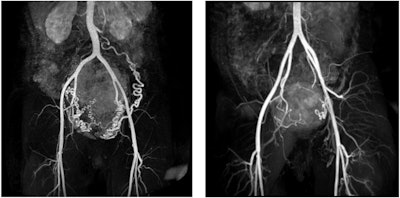

MR angiography images of subserosal/intramural uterine fibroid with a diameter of 144 mm in the dorsal uterine wall and hypertrophic arteria overica in a 41-year-old woman (left), and subserosal pedunculated fibroid of a 42-year-old woman with a 69 mm diameter (right).

MRI is used as the second-line modality when ultrasound cannot provide conclusive answers. "This may occur in selective cases when doubts exist regarding the benign/malignant nature of the supposed fibroid, or when MRI is necessary to assess eligibility for minimally invasive (uterine artery embolization) and non-invasive (MR-guided high-intensity focused ultrasound) treatments.”